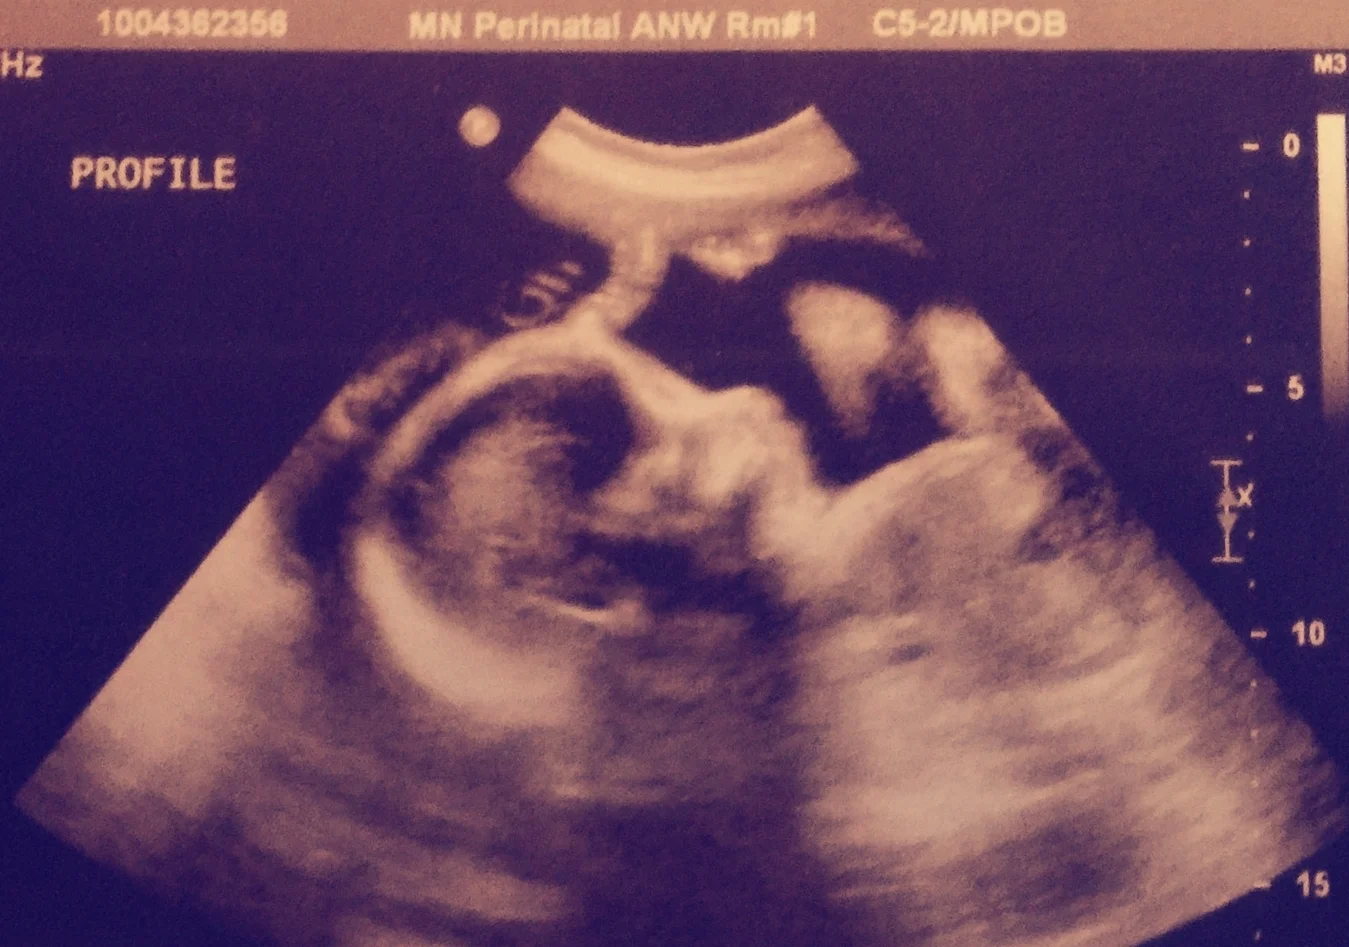

In January 2013 we slowly emerged from the sadness and grief of receiving the amniocentesis diagnosis. Another ultrasound indicated calcifications progressing toward the baby's heart and kidney arteries. In utero the calcifications represented a severe form of GACI. We were happy to know the baby was a girl and seemingly otherwise healthy. However, there was concern she may not survive the pregnancy. We were compelled to fight...for her life.

At 30 weeks pregnant, I started taking 2 tabs of Etidronate twice a day. Weekly at CHOP I met with Dr. Juan Martinez-Poyer a Maternal-Fetal medicine physician, Dr. David Goldberg, a Cardiologist and Dr. Michael Levine, the Chief of Endocrinology. The testing involved lab work and an ultrasound monitoring the calcifications in the baby. Something miraculous began to happen as each week the ultrasound results showed the calcifications were not advancing.